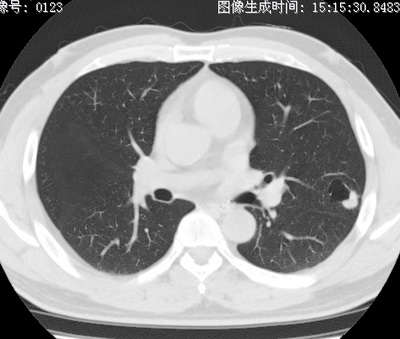

以下是引用zhao_bin2008在2010-1-4 20:15:00的发言:[br]先天性肺囊肿或小的肺隔离症?

以下是引用卜一在2010-1-4 22:09:00的发言:[br]先天性肺囊肿或小的肺隔离症?支持!

以下是引用zsl6918在2010-1-5 5:23:00的发言:[br]良性改变!肺囊肿,先天性支气管闭锁,血管畸形等均有可能。

以下是引用影像之路在2010-1-6 11:10:00的发言:[br]腺癌,最终的病检有些出乎意料之外,术前同志们大多考虑为肺囊肿或小的肺隔离征 [br]回过头来看 小结节呈分叶状,其内侧有一条较粗的静脉供血或许能成为支持诊断腺癌的理由